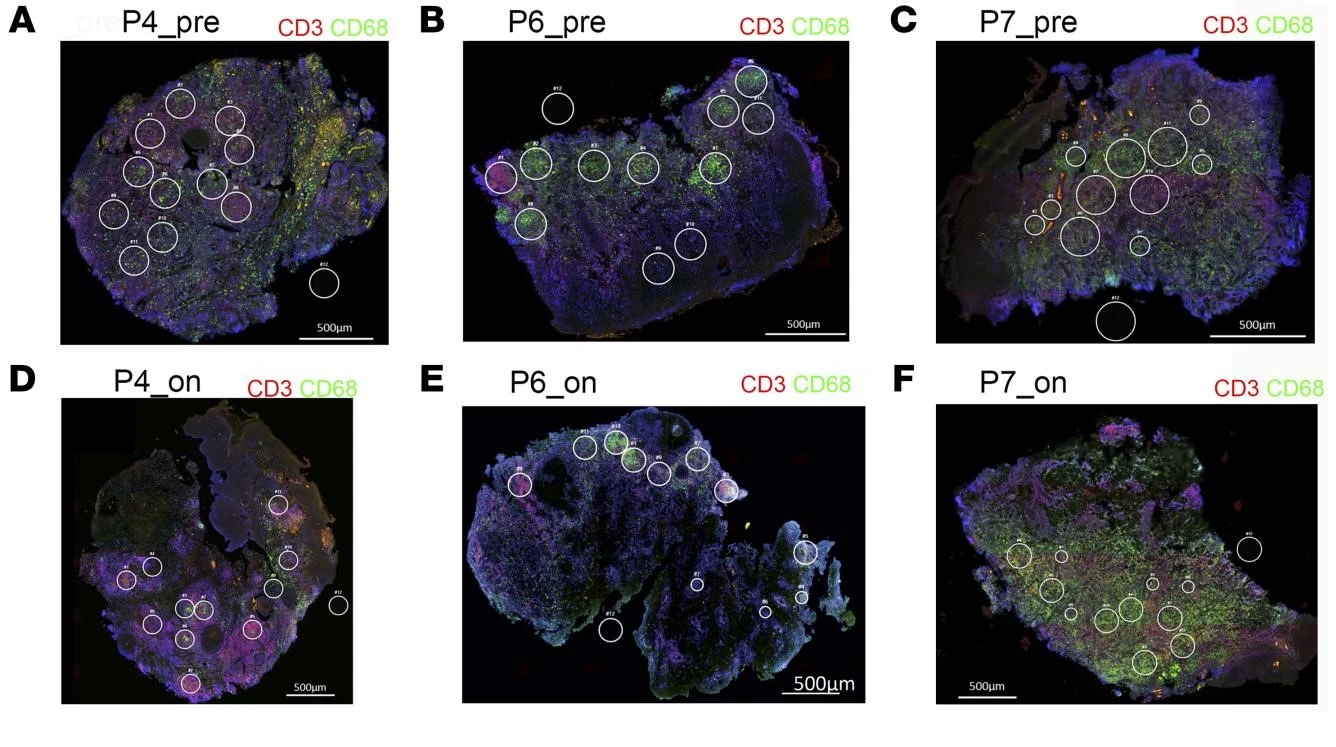

What is Spatial Phenotyping?

Spatial phenotyping combines whole-slide imaging and advanced analysis to study cellular phenotypes in their native context. This approach is key in immunotherapy research, enabling insights into the tumor microenvironment and supporting informed treatment strategies.